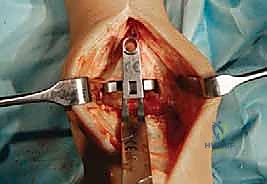

تُجرى العملية عادة تحت التخدير العام أو التخدير النصفي (الشوكي). يقوم د. هطيف بعمل شق جراحي أمامي أو جانبي (حسب التقنية المستخدمة وحالة المريض) للوصول إلى مفصل الكاحل بعناية، مع الحفاظ على الأوتار والأعصاب والأوعية الدموية المحيطة.

3. إزالة الأسطح التالفة (تحضير العظام)

باستخدام أدوات جراحية دقيقة وموجهات خاصة، يتم إزالة الغضاريف التالفة وجزء رقيق جداً من العظام المريضة من نهايتي عظمة الظنبوب وعظمة الكاحل (Talus). يتم تشكيل العظام بدقة لتتطابق تماماً مع شكل أجزاء المفصل الصناعي.

4. تركيب المفصل الصناعي (Implantation)

يتكون مفصل الكاحل الصناعي الحديث عادة من ثلاثة أجزاء:

* قطعة معدنية علوية: تُثبت في عظمة الظنبوب (الساق).

* قطعة معدنية سفلية: تُثبت في عظمة الكاحل.

* قطعة بلاستيكية (بولي إيثيلين عالي الكثافة): توضع بين القطعتين المعدنيتين لتنزلق بسلاسة وتمتص الصدمات، محاكيةً وظيفة الغضروف الطبيعي.

يتم تثبيت هذه الأجزاء بإحكام (إما عن طريق الضغط المباشر لتشجيع نمو العظم حولها، أو باستخدام أسمنت طبي خاص).

5. إغلاق الجرح والجبيرة